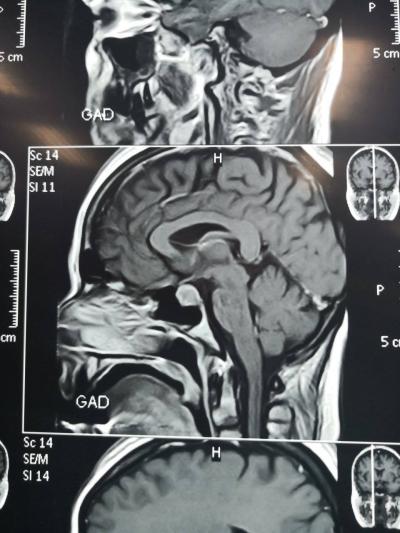

أجرى فريق طبي اختصاصي في مستشفى ابن سينا التعليمي/ الموصل عملية جراحية نوعية للغده النخامية المفرزة لهرمون الحليب غير المستجيب للعلاج عن طريق الأنف لمريضة في عقدها الرابع باستخدام أحدث ناظور للدماغ، وذلك يوم الاثنين 29 نيسان 2019. وتألف الفريق الطبي من كل من الأستاذ المساعد الدكتور هيثم عبدالملك النوري (تدريسي شعبة الانف والأذن والحنجرة فرع الجراحة كلية الطب جامعة الموصل)، وبمعيته كل من الجراح الاختصاص الدكتور محمد نذير الزبيدي اختصاص الجراحة العصبية وفريق التخدير بقياده الدكتور محمد ذنون ومساعد مخدر ايمن لقمان و ياسر احمد ومساعد جراح ياسر فتحي ومسؤول صالة العمليات علي اسماعيل (وهم من دائرة صحة نينوى). ولله الحمد، فقد تكللت العملية بالنجاح بعدما اخضعت المريضة الى وحدة العناية الفائقة وتلقت العلاج اللازم. وتمت متابعة حالة المريضة لحين خروجها، وهي تنعم بالصحة والعافية، حيث عاد الهرمون الى مستواه الطبيعي.. مبارك للدكتور النوري هذا التألق والعطاء، ومن الله التوفيق.